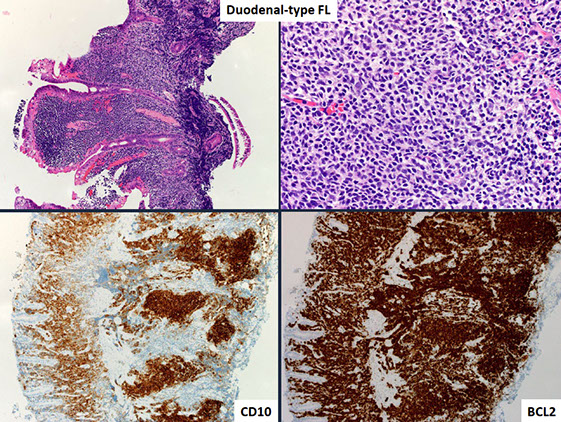

- Duodenal-type FL